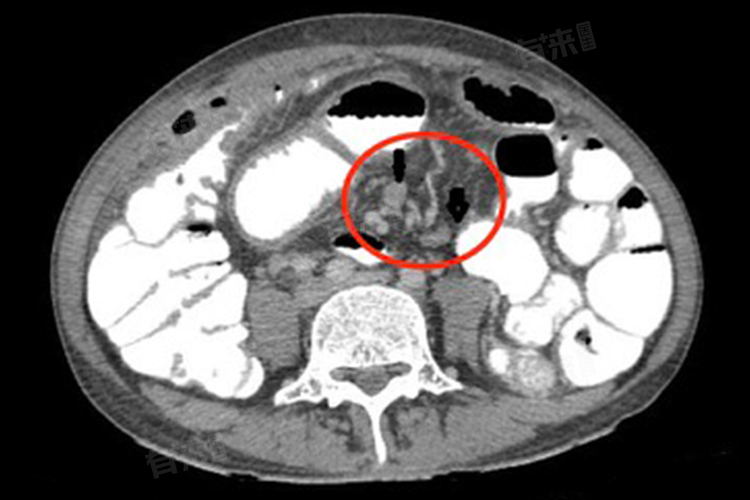

- 腹腔淋巴结肿大可能会引起一系列的症状,如果肿大的淋巴结压迫周围的器官或组织,可能会出现腹痛、腹胀、恶心、呕吐等症状。如果是炎症引起的淋巴结肿大,患者可能还会伴有发热、乏力等全身症状。在诊断腹腔淋巴结肿大时,医生通常会结合患者的病史、症状、体征以及各种检查结果进行综合判断。常用的检查方法包括腹部超声、CT、磁共振成像等影像学检查,以及血液检查、肿瘤标志物检测等。